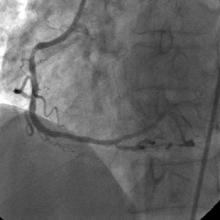

Angiography

3) LAD: Ostial CTO ( Figure 2) with collaterals from RCA and LCX (Figure 3).